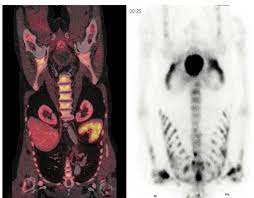

Https Onlinelibrary Wiley Com Doi Pdf 10 1002 Pros 2990250305

Https Onlinelibrary Wiley Com Doi Pdf 10 1002 Pros 2990250305 from